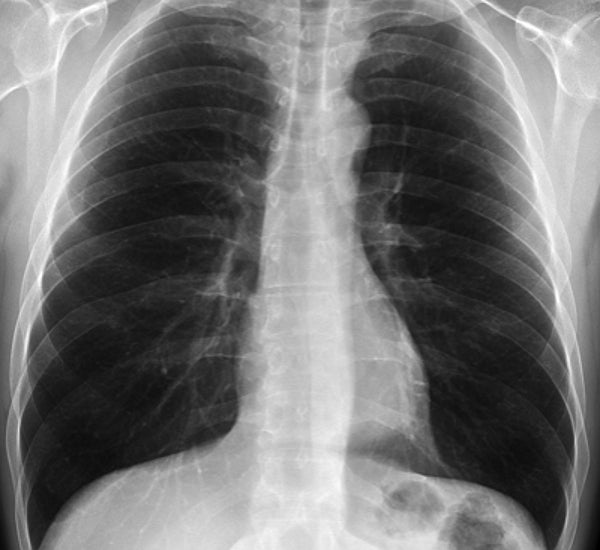

Se trata de las radiografías de dos personas que provenían de Wuhan, China. En ellas, se observa que en sus pulmones hay una importante reducción del espacio funcional de sus órganos respiratorios.

Deteriorados y con un avanzado daño se ven los pulmones de dos pacientes, quienes fueron los primeros casos positivos por COVID-19 en Italia.

Ambos, provenientes de Wuhan, China, fueron sometidos a una toma de imágenes de tórax, cuyos resultados radiográficos y tomográficos revelaron un importante avance de esta enfermedad respiratoria.

Tanto en el caso del hombre, como el de la mujer -ambos mayores de 65 años-, se observa que en sus pulmones hay una importante reducción del espacio funcional de sus órganos respiratorios.

Al momento de publicar los resultados de la investigación, los autores señalaron que ambos pacientes se encontraban en condición crítica, pero estable al momento en que tomaron las imágenes radiográficas.

Además, aseguraron que el estudio reveló que los vasos sanguíneos que llevan la sangre del corazón a los pulmones, para su oxigenación, se estaban dilatando. Este aumento de tamaño, conocido como hipertrofia, reduce el espacio para el aire y provoca la dificultad para respirar.

Sin embargo, el descubrimiento de la progresión de la enfermedad en estas imágenes, permite a los expertos describir un signo radiológico de infección temprana ante una insuficiencia pulmonar, por lo que permitiría avecinar un patrón para enfrentar las dificultades respiratorias en los pacientes contagiados por coronavirus.